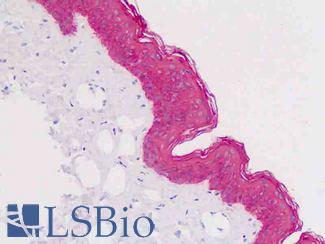

EGFR

Anti-EGFR antibody IHC of human skin. Immunohistochemistry of formalin-fixed, paraffin-embedded tissue after heat-induced antigen retrieval. Antibody LS-B2914 concentration 5 ug/ml.